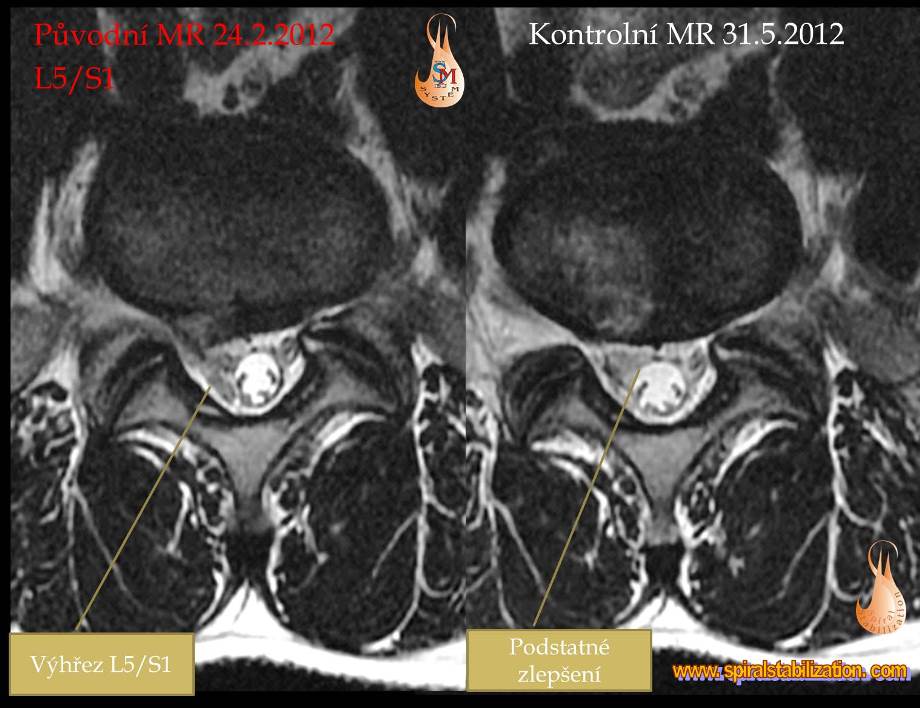

Výsledky hernia L5/S1